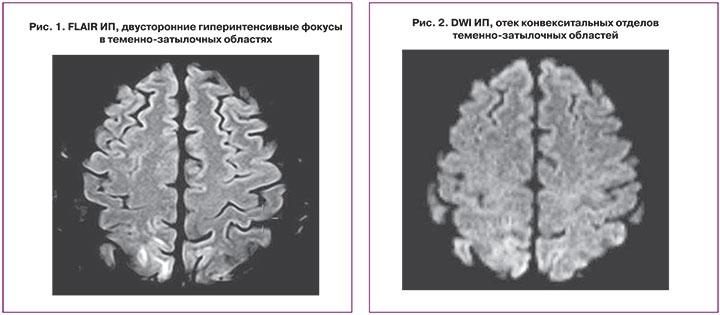

Пациентка переведена в отделение реанимации и интенсивной терапии, где проводилось динамическое наблюдение, клинико-лабораторное дообследование, седативная, магнезиальная, антигипертензивная, гепатопротекторная терапия, профилактика тромбоэмболических осложнений. За первые сутки в отделении проведен ряд инструментальных исследований: мультиспиральная компьютерная томография органов грудной клетки и ультразвуковое исследование (УЗИ) почек и мочевого пузыря – патологии не выявлено; УЗИ органов брюшной полости: признаки гепатомегалии, хронического калькулезного холецистита; МРТ головного мозга: МР-признаки отека коры головного мозга в теменных и затылочных отделах, в задних отделах мозолистого тела и мозжечке справа – «синдром задней обратимой энцефалопатии» (рис. 1, 2).

На 4-е сутки после родов переведена в послеродовое отделение. В динамике отмечается улучшение общего состояния, регресс жалоб, пациентка более активна, АД в пределах нормальных значений, судороги не повторялись. На контрольной МР-томограмме на 4-е сутки после родов отмечается почти полное обратное развитие признаков PRES (рис. 3, 4).